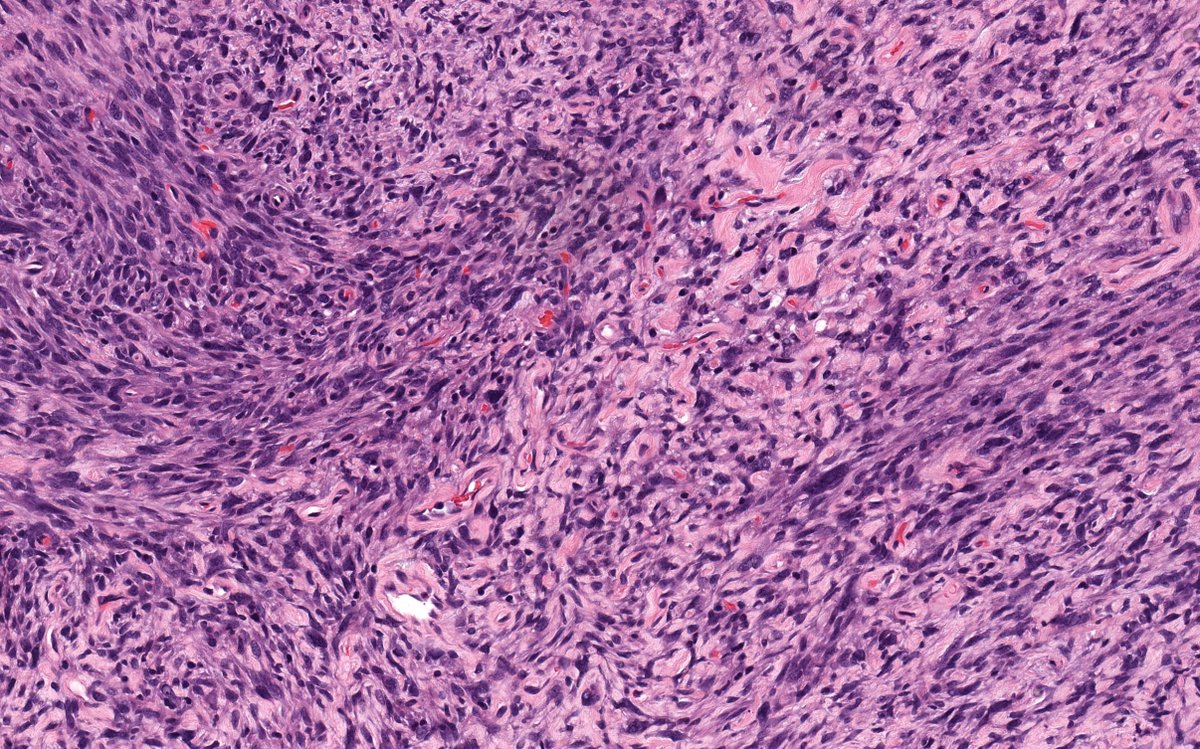

ERBB2/ ERBB3-mutated S100/ SOX10-positive unclassified high-grade uterine sarcoma: first detailed description of a novel entity

Virchows Archiv - With the increasing use of innovative next generation sequencing (NGS) platforms in routine diagnostic and research settings, the genetic landscape of uterine sarcomas has been...

Tumors in the skin with the morphology of leiomyosarcoma (B-D) but that are confined to the dermis (no subcutis infiltration) are termed atypical intradermal smooth muscle tumors (AISMT). This distinction is made as AISMT can recur, but has no metastatic potential. #DermPath